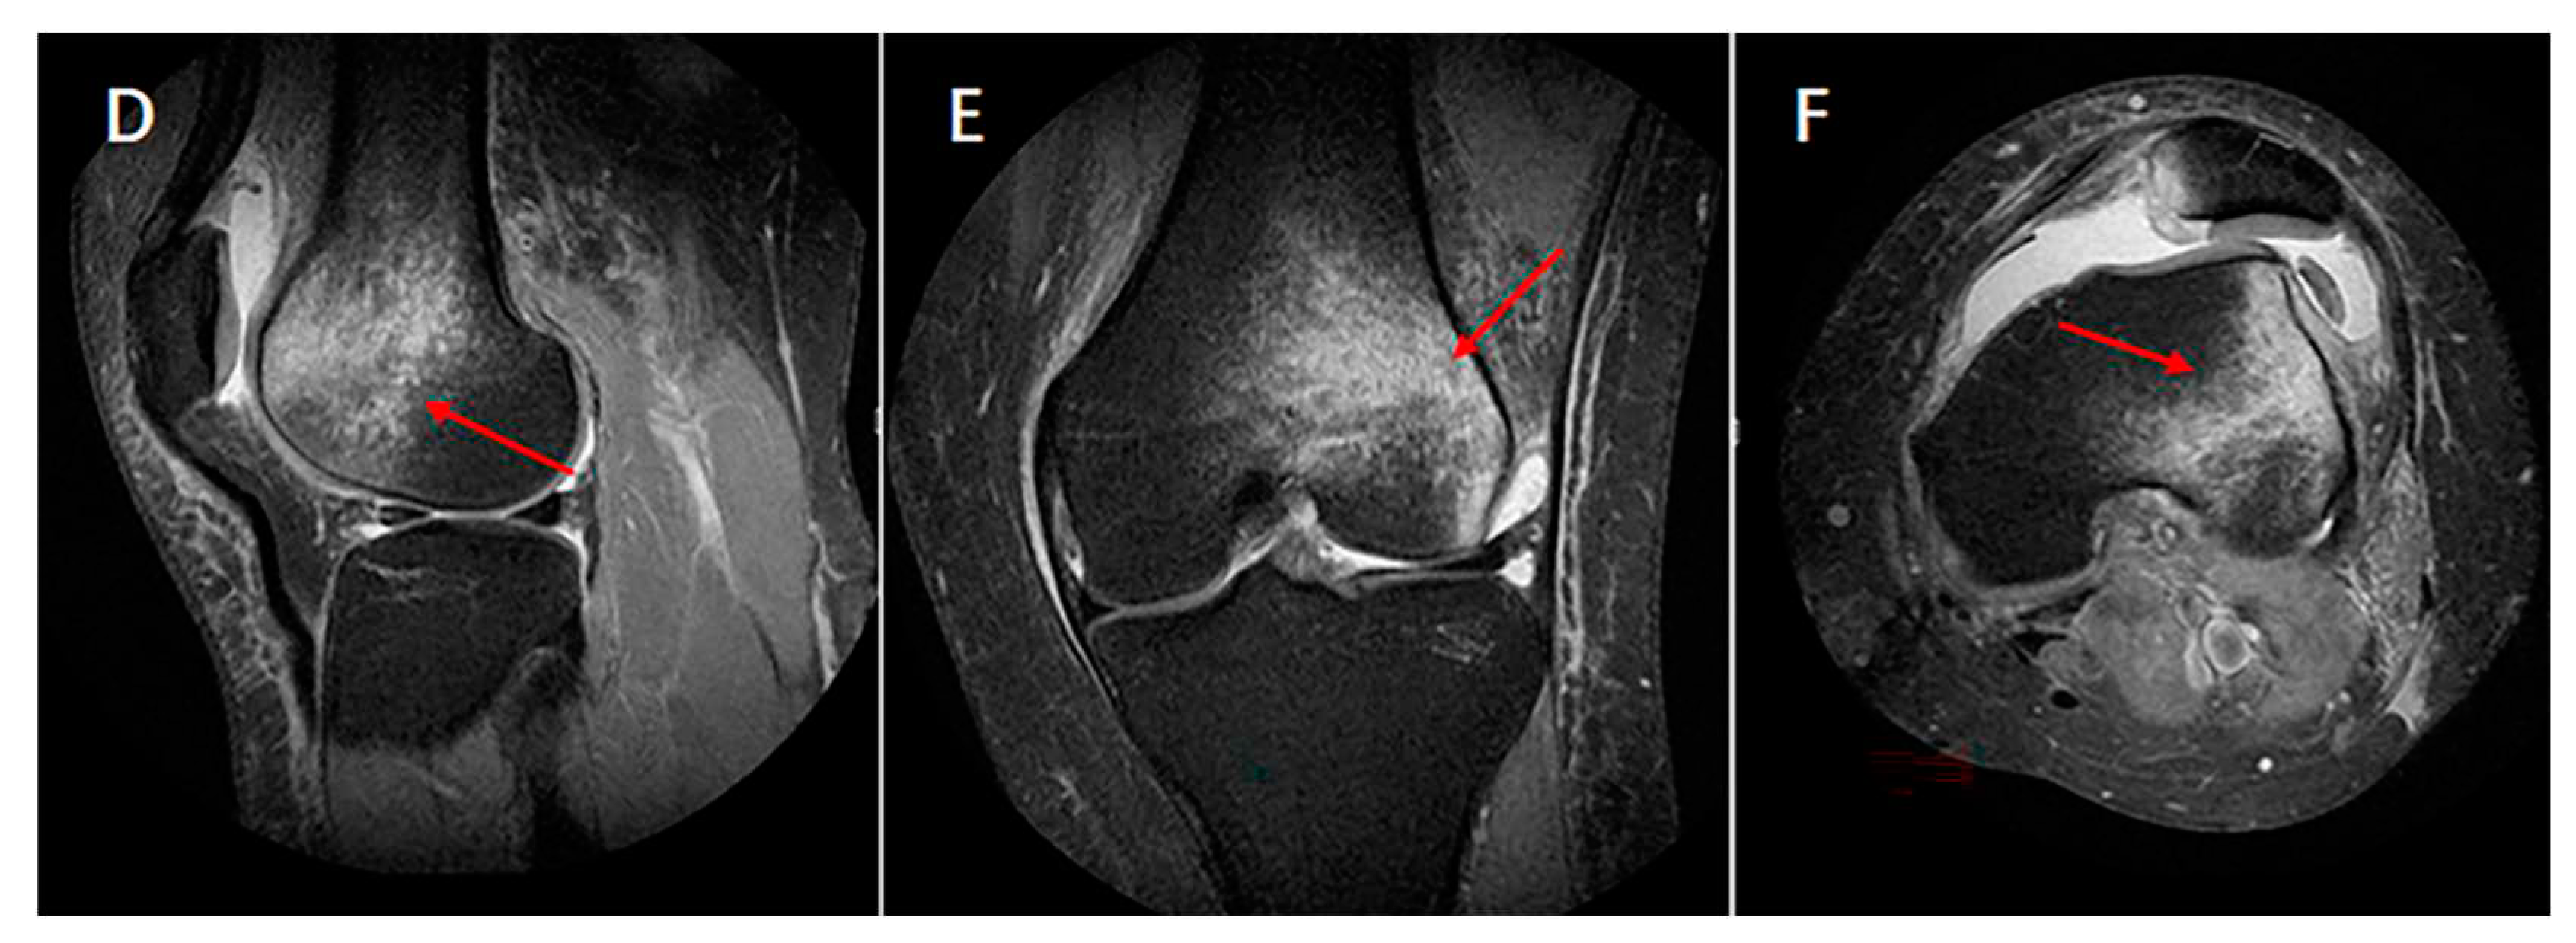

By calculating the position of bone bruises in sagittal and transvers planes, there was only 1 pattern bone bruise (latera femur and medial patella bone bruise) of patellar dislocation (Figure 4), bone bruise was in the inferior medial patella and lateral anterior inferior femur (Table 3), and seven categories of bone bruises characteristics were obtained as follows, MIP+LAIF (medial inferior side of patellar and lateral anterior inferior side of femur, 57%); MIP+LPIF (medial inferior side of patellar and lateral posterior inferior side of femur, 22%); MIP+LASF (medial inferior side of patellar and lateral anterior superior of femur, 10%); MSP+LAIF (medial superior side of patellar and lateral anterior inferior side of femur, 6%); MIP+LPSF (medial inferior side of patellar and lateral posterior superior side of femur,1%); MSP+LASF (medial superior side of patellar and lateral anterior superior of femur,1%); MSP+LPIF (medial superior side of patellar and lateral posterior inferior side of femur,1%).

Figure 4. Distribution of patellar bone bruise in three planes of patellar dislocation patients. A(D), sagittal plane; B€, coronal plane; C(F), transverse plane. Red arrow, femoral bone bruise. Green arrow, patella bone bruise.

To test our hypotheses, we reviewed the MR images ACL rupture and patellar dislocation patients with bone bruises. Imaging sequences of the sagittal and transverse planes were used to quantitatively calculated relative lateral-medial and superior-inferior direct positions of bone bruises in distal femur, proximal tibia and patella. As showed in our study, there were 4 (1-,2-,3-,4-) kinds of bone bruise patterns of ACL rupture, and the commonly seen bone bruise patterns were 3- (LF+BT, BF+LT, MF+BT) , followed by 4 (BF+BT) and 2- (LF+LT, MF+LT, LF+MT, MF+MT, 0+BT; Table 2) bone bruises in femur and tibial respectively while there was only 1 pattern of patellar dislocation which in lateral femur and medial patella (Figure 1 and Figure 2, Table 3). ACL rupture and patellar dislocation have the completely different bone bruise patterns which may represents the different injury mechanisms of the knee. The ACL rupture patients who displayed 1- bone bruises of femur and tibia respectively, suggesting that the knee displayed anterior and translated tibia to the femur at the time of injury. The ACL rupture patients who displayed 3- or 4- bone bruises in 1- or 2- femur and 2- tibia suggesting that the knee joint was unstable when ACL was injured, not only anterior and translated tibia to the femur but also shaking obviously in the lateral-medial direction was performed of the knee at the time of injury. Similarly, the difference of the superior-inferior direct positions of femoral and patellar bone bruises in patellar dislocation also indicated that different bone bruise patterns reflect different knee flexion angles at the time of injury (Figure 4 and Figure 5).